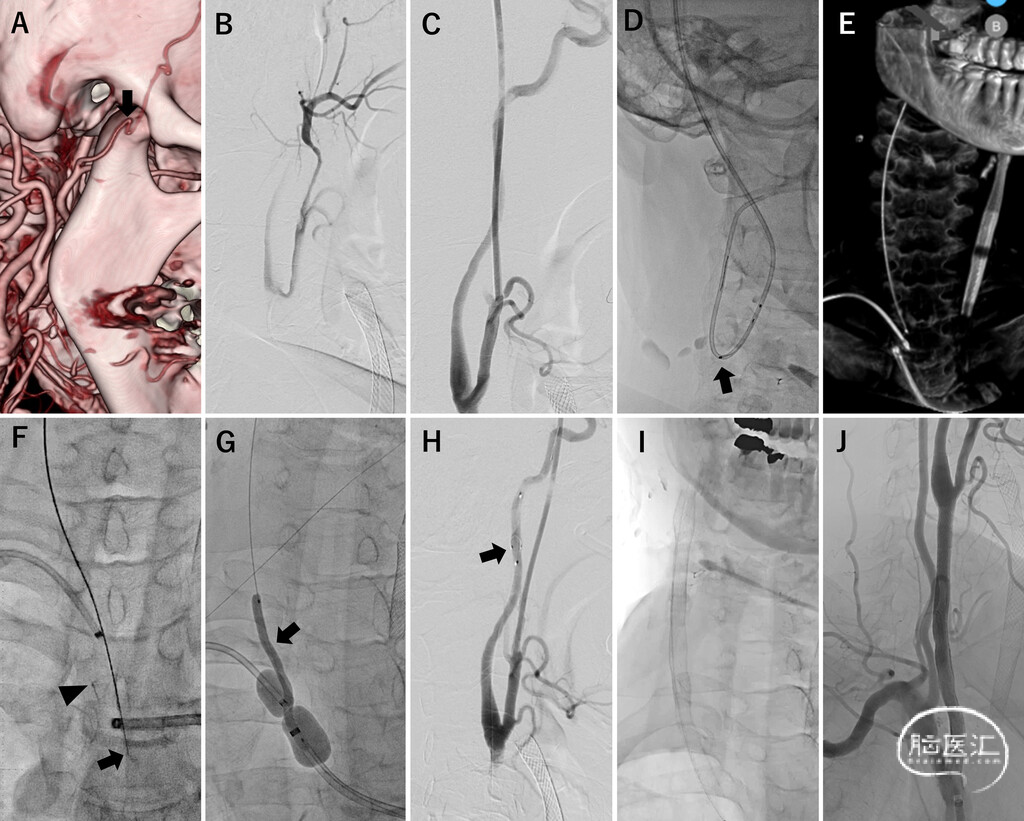

FIG. 3. Retrograde approach for right CCA chronic occlusion with carotid artery stent insertion. A: Three-dimensional CT angiogram showing that the diameter of the right STA at the planned puncture site (arrow) was 1.0 mm. B: The STA was punctured with a 21-gauge Surflo needle, and an image was taken from the Surflo. C: A 5-Fr Glidesheath Slender sheath was placed in the external carotid artery. D: A 4-Fr catheter was guided into the ICA, and an attempt was made to guide a SpiderFX device (arrow); however, it could not be guided because of a sharp bend. E: Cone-beam CT was used to confirm that the Fencer microcatheter was located at the origin of the CCA. F: An Astato XS 9–12 guidewire (arrow) was used to penetrate the occluded site. It was then captured with a snare (arrowhead) and pulled through the guiding catheter from the femoral artery approach. G: The balloon-guiding catheter was inflated to sandwich the CCA, and balloon angioplasty (arrow) was performed under blood flow occlusion. H: An external carotid artery angiogram was obtained from the STA puncture sheath. A filter protection device (arrow) was guided into the right ICA using a guidewire that was pulled through. I:Three stents were deployed in a connected manner. J: Brachiocephalic artery angiogram revealing good expansion of the CCA.